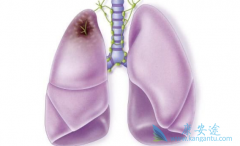

肺癌晚期怎么治疗能延长患者的生存时间

在众多癌症中,肺癌往往给人既熟悉又可怕的印象。说熟悉它,是因为从小就知道吸烟会得肺癌;说它可怕,是因为肺癌的发病率和死亡率在所有恶性肿瘤中都是名列前茅的。早期肺癌症状不明显,甚至是没有任何不适的感觉,而往往发现时就已经到了晚期,出现了 ...